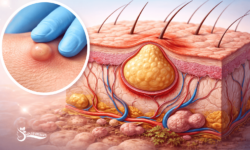

ماینوکسیدیل در اصل بهعنوان یک گشادکننده عروق شناخته میشود. وقتی این دارو بهطور موضعی روی پوست سر استفاده میشود، باعث اتساع رگهای خونی کوچک اطراف فولیکولهای مو میگردد. این افزایش جریان خون، اکسیژن و مواد مغذی بیشتری را به ریشه مو میرساند. نتیجه این فرآیند، تقویت متابولیسم سلولی فولیکول و فراهم کردن محیطی مناسب برای رشد موهای قویتر و ضخیمتر است. در واقع میتوان گفت ماینوکسیدیل به فولیکولهایی که در حال ضعیف شدن هستند “سوخت و انرژی” تازهای میدهد.

بر اساس تحقیقات آزمایشگاهی، ماینوکسیدیل تأثیر مستقیم بر سلولهای پاپیلای پوستی دارد. این سلولها مسئول تولید پروتئینها و فاکتورهای رشدی هستند که رشد مو را تحریک میکنند. ماینوکسیدیل با فعالسازی کانالهای پتاسیمی و افزایش تولید پروتئینهایی نظیر VEGF (Vascular Endothelial Growth Factor) باعث بهبود خونرسانی و تحریک فولیکولها میشود. همچنین این دارو بر متابولیسم سلولی اثر گذاشته و چرخه حیات فولیکول را طولانیتر میکند. در نتیجه موهای نازک و کرکی (vellus hair) بهتدریج ضخیمتر و به موهای ترمینال تبدیل میشوند.